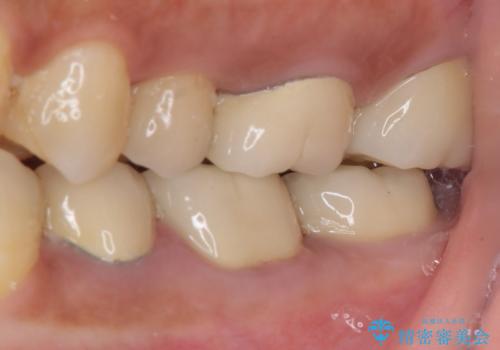

食事で痛む 神経を極力残した虫歯治療

- 食事中にしばしば痛みを感じるとのことで来院された患者様です。

診査をしたところ、レントゲン写真よりとても大きなむし歯があることが分かりました。

後日状態を確認したところ、残された神経に異常がなかったため、セラミッククラウンにて補綴治療を行いました。